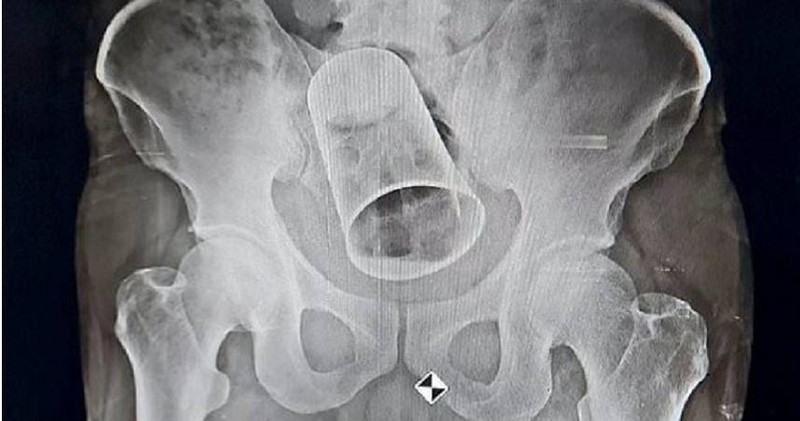

Tại bệnh viện, bác sĩ đã chụp X-quang để xác định vị trí chiếc cốc. Qua phim chụp, bác sĩ không khỏi ngỡ ngàng khi thấy chiếc cốc thép này có đường kính lên đến 8 cm và dài 15 cm. Ban đầu, bác sĩ muốn trực tiếp lấy chiếc cốc thép mắc kẹt trong hậu môn ra nhưng chiếc cốc thép quá to nên cuối cùng phải tiến hành phẫu thuật cắt ruột.

Ca mổ kéo dài 2,5 giờ, hiện người đàn ông đang hồi phục và tình trạng ổn định. Qua chuyện này, bác sĩ nhắc nhở mọi người, tuyệt đối không nên chơi khăm, đùa ác làm tổn hại đến cơ thể người khác, bằng không sẽ để lại hậu quả rất nghiêm trọng.